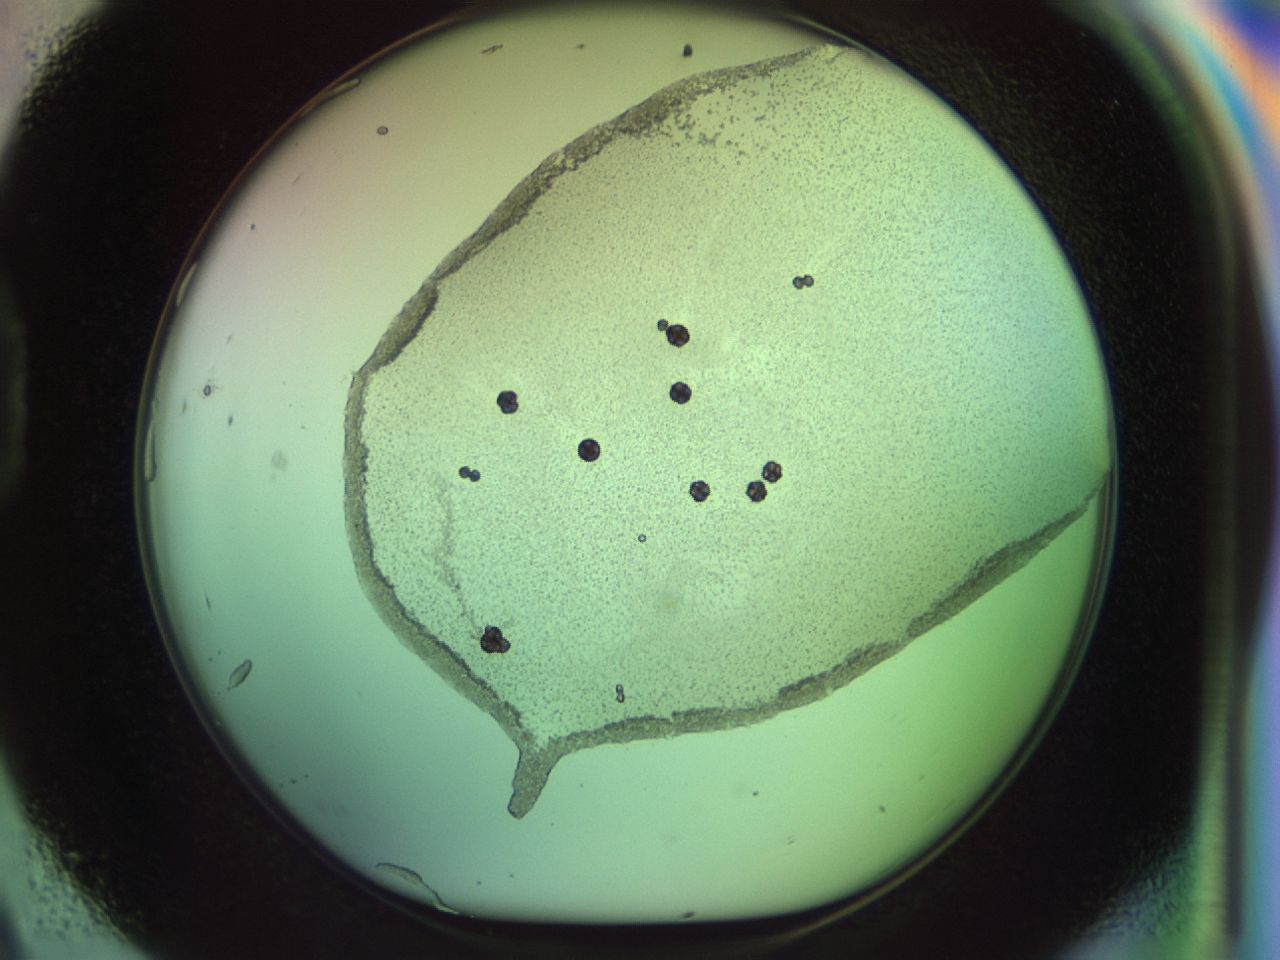

Image 11752

02nu_D9_ImagerDefaults_5.jpg